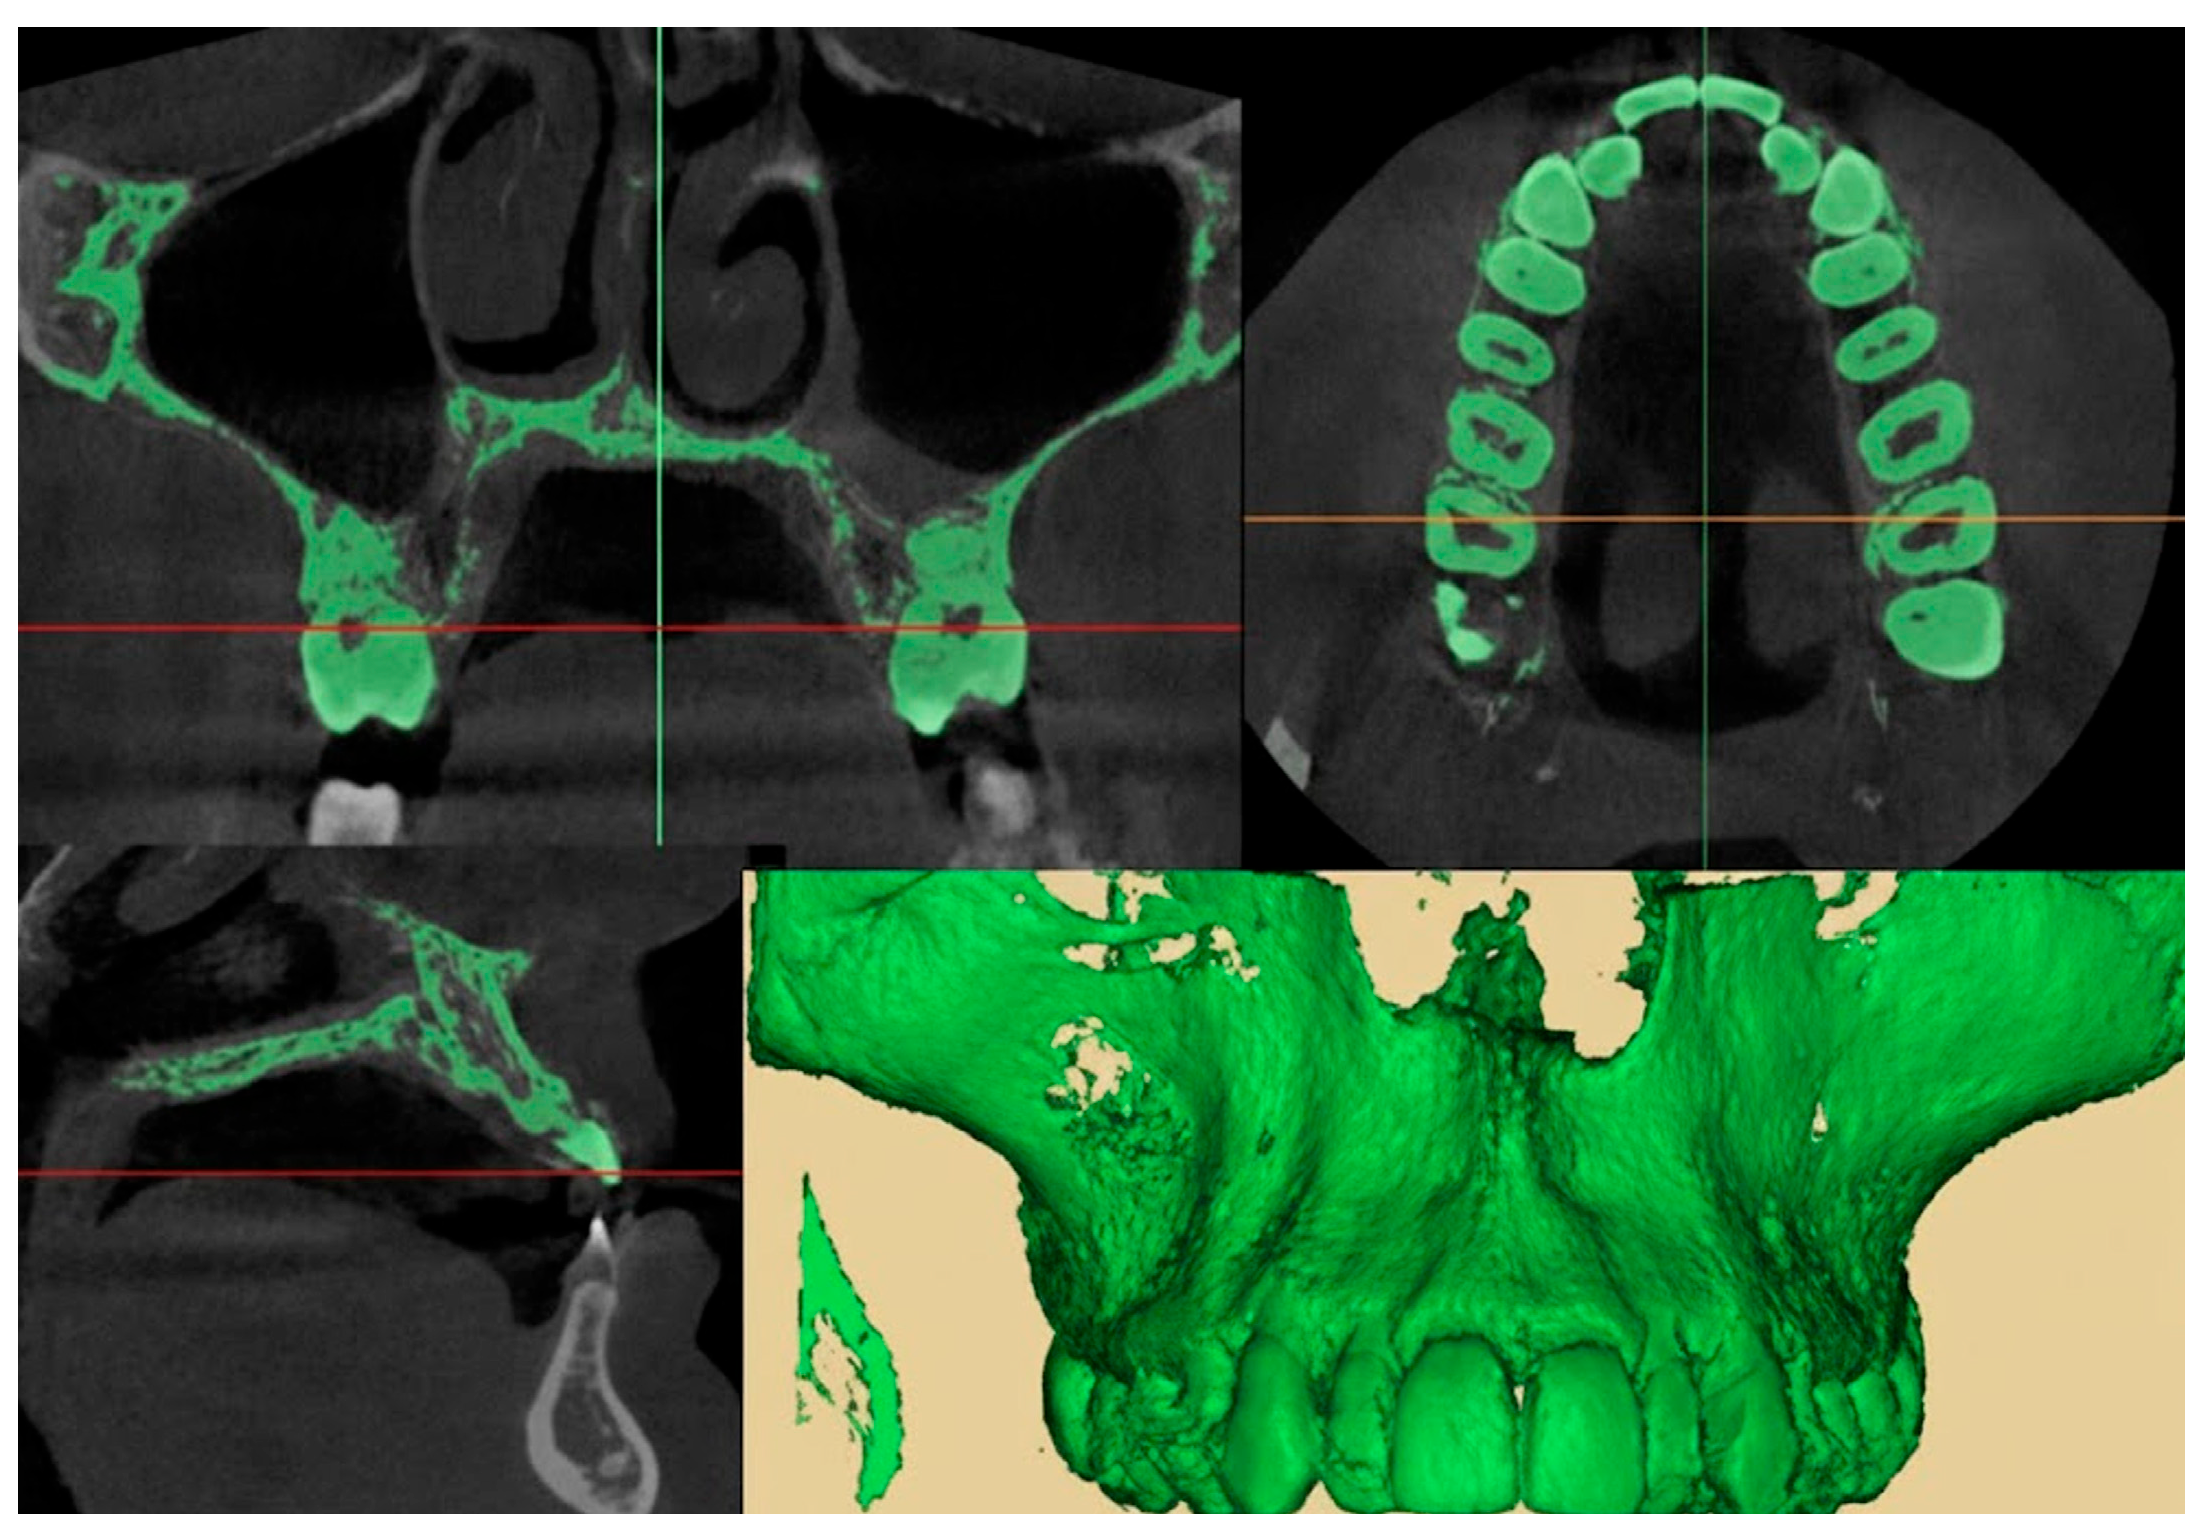

2.9.1. Qualitative Evaluation of Maxillary Expansion on Cone Beam Computed Tomography

2.9.2. Quantitative Two-Dimensional Analysis of Upper Palatal Expansion on CBCT

2.9.3. Evaluation of Dental Effects: Alveolar Bending, Palatal Alveolar Angle, Dental Tipping and Bone Dehiscence

3.2. Qualitative Evaluation of Maxillary Expansion on Cone Beam Computed Tomography

3.3. Quantitative Two-Dimensional Analysis of Upper Palatal Expansion on CBCT

3.4. Evaluation of Dental Effects: Palatal Alveolar Angle, Buccal Tipping Angle, Bone Dehiscences and Fenestrations